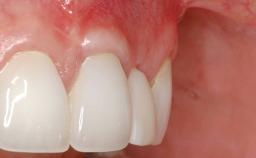

Soft-Tissue Volume Augmentation Using a Connective-Tissue Graft Harvested from the Maxillary Tuberosity

In 1983, a 51-year-old non-smoking patient was referred for the treatment of moderate chronic periodontitis. At the initial examination, 47% of sites exhibited probing depths of 4 to 6 mm. Periodontal therapy consisted of initial periodontal treatment including oral-hygiene instructions and supra- and subgingival debridement, followed by periodontal surgery to eliminate residual pockets.